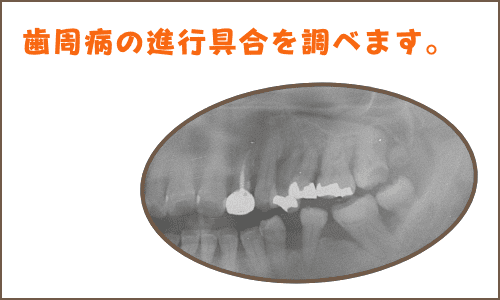

一般的に後者の方が、歯周病の進行が進んだ状態だと言われていますが、レントゲン撮影によって、顎の骨の吸収程度を見たり、歯周ポケット検査などで総合的に診断する必要があります。

抜くかどうかはレントゲン撮影で骨の状態を確認

さて、ご質問のグラグラした歯ですが、単に揺れているというだけで、歯を抜く訳ではありません。歯がグラグラしていても、レントゲン撮影をしたら歯の周りの骨がまだ保存可能な状態のこともよくあります。